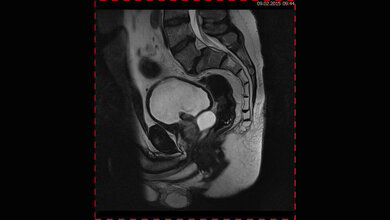

Rund 275.000 Menschen waren im Jahr 2020 laut MedUni Wien mit der Diagnose Blasenkrebs konfrontiert, 108.000 Personen sind daran verstorben – ein Drittel bis ein Viertel der Neuerkrankungen betrifft Frauen. Diese erleiden diese Form des Krebses also seltener als Männer, haben aber bei der Diagnose bereits ein deutlich höheres Tumorstadium und eine schlechtere Prognose. Die Gründe sind vielfältig, wie Shahrokh Shariat, Leiter der Universitätsklinik für Urologie der MedUni Wien, anlässlich des internationalen Blasenkrebs-Monats Mai betont, und liegen in molekularen, immunologischen, aber auch geschlechtsspezifischen Faktoren begründet, wie aktuelle Studien der MedUni Wien zeigen. Daher müsse man künftig noch mehr als bisher bei der Vorsorge, Therapie und auch bei nötigen Eingriffen personalisierte, individuelle Modelle – Stichwort Präzisionsmedizin – anwenden.

Aber auch dann, wenn Blasenkrebs bereits diagnostiziert wurde, seien Frauen wesentlich stärker betroffen als Männer. Shariat und sein Team haben nicht nur herausgefunden, dass Frauen mit Blasenkrebs in jedem Stadium der Erkrankung eine deutlich schlechtere Prognose haben, sondern auch, dass sich die Prognose im Gegensatz zu den Männern über die vergangenen Jahrzehnte nicht verbessert hat. Das Forschungsteam der MedUni Wien hat im vergangenen Jahr auch beweisen können, dass Frauen weniger auf die Immuntherapie, jedoch besser auf eine Chemotherapie ansprechen. Gerade vor einer Operation sollte daher bei Frauen verstärkt auf eine Chemotherapie gesetzt werden.